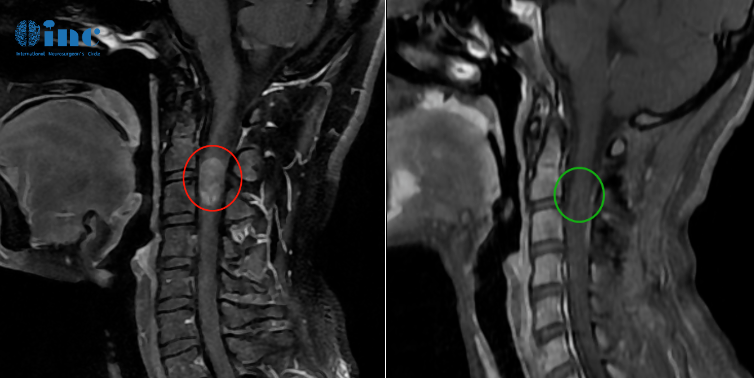

患者情况:28岁的潇潇6年前开始出现肩部至腰部疼痛,刚工作的她以为是工作疲劳导致的,并未引起特别重视,只是定期进行按摩治疗。然而两年前,潇潇肩部后侧疼痛加剧,于当地医院行磁共振检查,提示髓内占位性病变,保守治疗无效。2021年7月行增强磁共振提示C3水平占位,直径7mm。当地医院排除炎性病变。因考虑到手术风险大,未作手术治疗。2021年10月复查磁共振提示影像较前大致相仿。2022年6月磁共振提示大小约8*12*14mm。2022年10月磁共振提示8*12*19mm。肿瘤持续进展,年轻的潇潇不愿意继续坐以待毙,等待脊髓髓内这颗炸弹引爆自己的生命,于是她开始四处寻求能够为自己顺利手术的主刀医生。在病友的下,她开始了解到这次为她成功手术的——INC德国巴特朗菲教授。